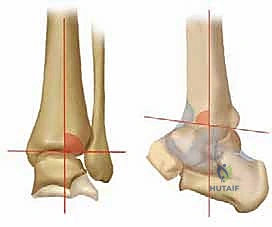

2. التصوير بالأشعة السينية بوضعية الوقوف (Weight-bearing X-rays)

هذا هو حجر الأساس في التشخيص. الأشعة العادية والمريض مستلقٍ لا تظهر الحجم الحقيقي للتشوه. يطلب الدكتور هطيف صوراً خاصة والمريض يحمل وزنه كاملاً على قدميه.

* المنظر الأمامي الخلفي (AP View): لتقييم المسافة المفصلية وتحديد زاوية سطح الساق (Tibial Anterior Surface Angle - TAS).

* منظر سالتزمان (Saltzman View): وهو منظر إشعاعي متخصص جداً لتقييم محاذاة الكعب الخلفي بالنسبة لمحور الساق، وهو أمر حاسم في التخطيط الجراحي.